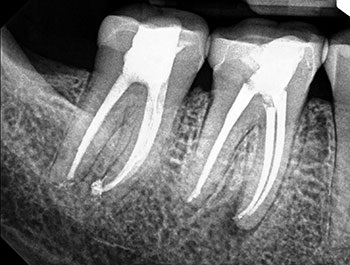

Case 10: Failing ‘well done’ NSRCT

This patient’s teeth #30 and #31 were treated by an endodontist. The endodontist found all the canals, achieved patency and shaped and filled each canal to length. When the periradicular tissues surrounding both teeth failed to heal, the endodontist recommended extracting both teeth because of VRFs. By then, tooth #31 developed a J-shaped lesion, suggestive of a VRF. Nothing suggested that tooth #30 had a VRF, other than that it was a “good-looking” or “well-done” NSRCT that failed. Yet both were recommended for extraction.

The somewhat skeptical patient came to see if these teeth really needed to be extracted. Nonsurgical retreatment was recommended. The patient didn’t want to lose his teeth, but he also didn’t want to pay to re-treat teeth that could not be saved.

Tooth #31—the tooth that was more likely to be fractured—was addressed first. To maximize the likelihood of healing, this tooth was treated in multiple visits using a calcium hydroxide intracanal medicament and obturated after bony healing was complete. The patient was delighted that his tooth had been saved, but also somewhat perplexed that the original endodontist gave up on a tooth that could have been saved. He has now scheduled re-treatment for tooth #30.

More than a few cases have been seen for second opinions after a dentist completed RCT on a tooth that failed shortly after, then told the patient to extract the tooth because it must be cracked because the NSRCT “looked perfect” radiographically. Although shaping and obturation can be judged radiographically, the most important factor—disinfection—cannot.

Fig.39: Preop CBCT.

Fig.40: Postop PA.

Fig.41: Recall PA.